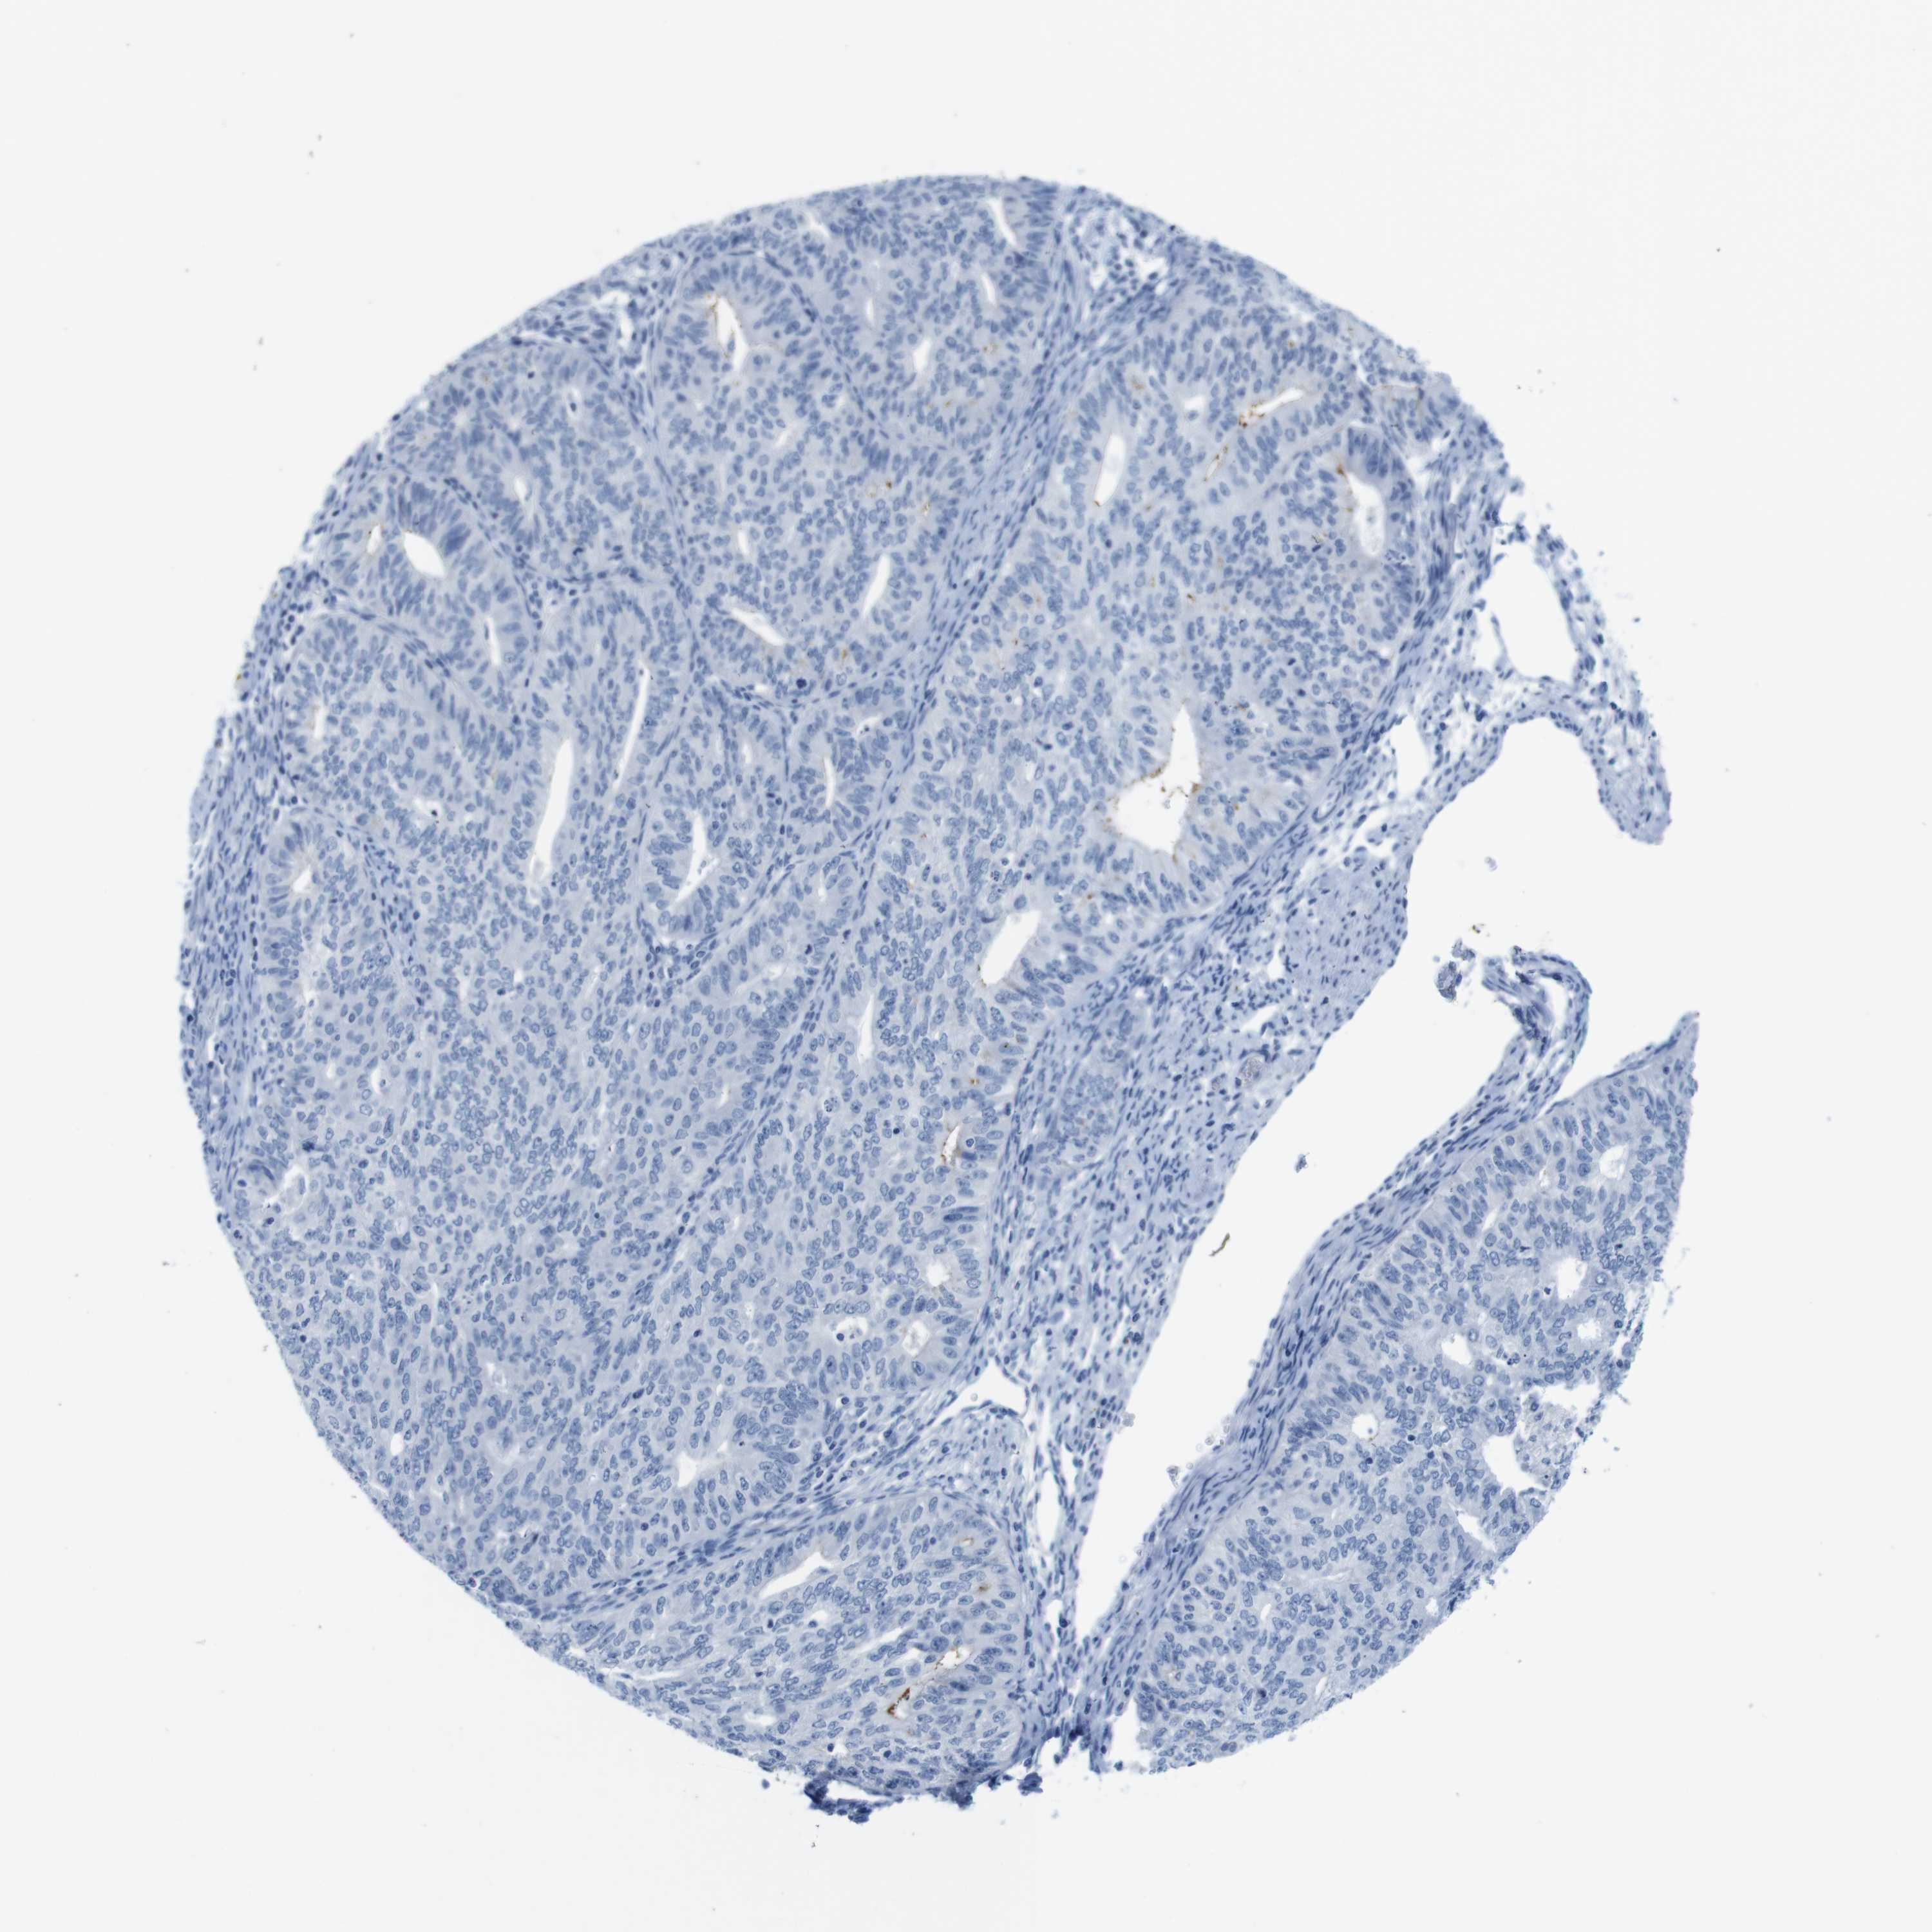

ENDOMETRIAL CANCER - Protein expressioni

A mouse-over function shows sample information and annotation data. Click on an image to view it in a full screen mode. Samples can be filtered based on level of antibody staining by selecting one or several of the following categories: high, medium, low and not detected. The assay and annotation is described here.

Note that samples used for immunohistochemistry by the Human Protein Atlas do not correspond to samples in the TCGA dataset.

Antibody stainingi

Antibody staining in the annotated cell types in the current human tissue is reported as not detected, low, medium, or high, based on conventional immunohistochemistry profiling in selected tissues. This score is based on the combination of the staining intensity and fraction of stained cells.

Each image is clickable and will lead to virtual microscopy that enables deeper exploration of all samples and also displays staining intensity scores, fraction scores and subcellular localization as well as patient and tissue information for each sample.

Antibody HPA039061

Antibody HPA039062

Antibody CAB015442

Antibody CAB022600

Staining

High

Medium

Low

Not detected

Intensity

Strong

Moderate

Weak

Negative

Quantity

>75%

75%-25%

<25%

None

Location

Nuclear

Cytoplasmic/membranous

Cytoplasmic/membranous,nuclear

Adenocarcinoma, NOS